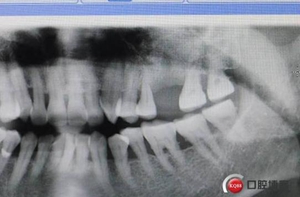

六個(gè)月之后